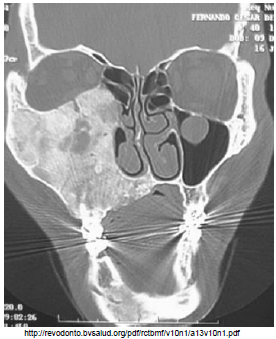

Paciente, sexo masculino, 32 anos, apresenta abaulamento progressivo e dor no terço médio da hemiface direita há quatro anos. Realizou tomografia computadorizada.

Marque a opção correta sobre a lesão apresentada na imagem acima.